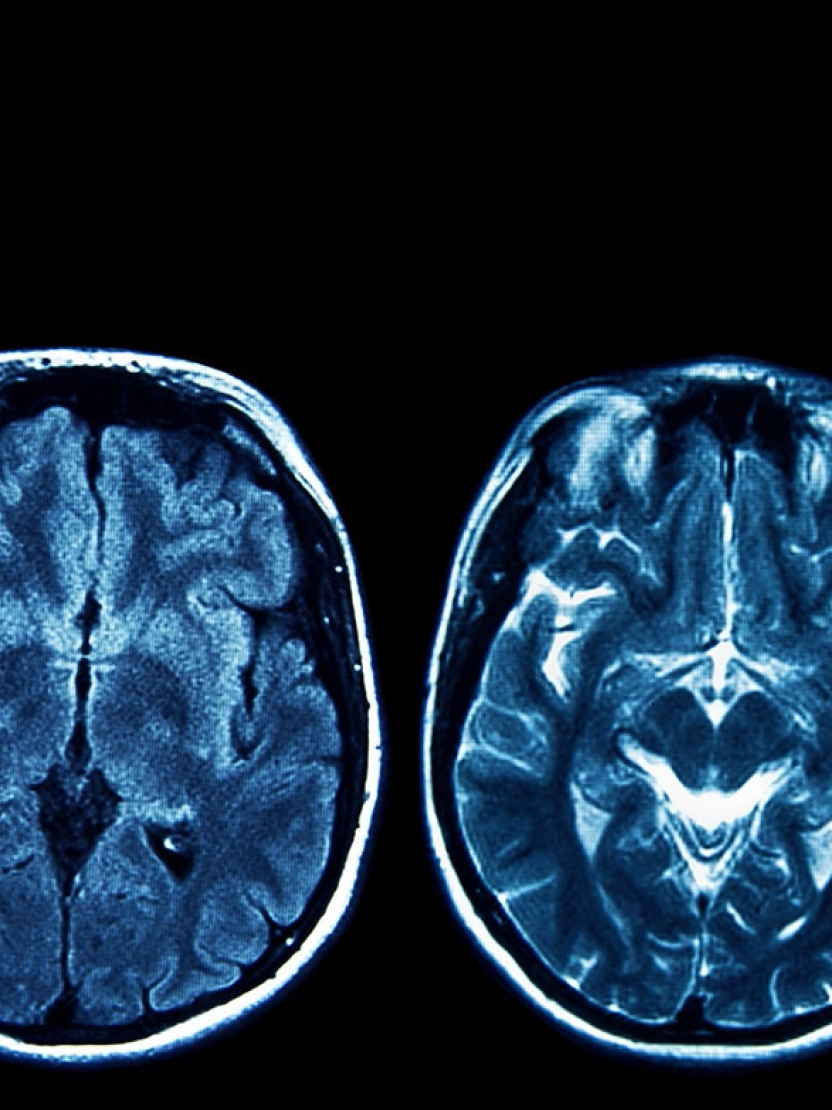

During HBOT, oxygen dissolves more effectively into the bloodstream, allowing it to reach areas where circulation may be limited. This increased availability may support processes involved in recovery and help your body respond more efficiently to physical strain and daily demands.